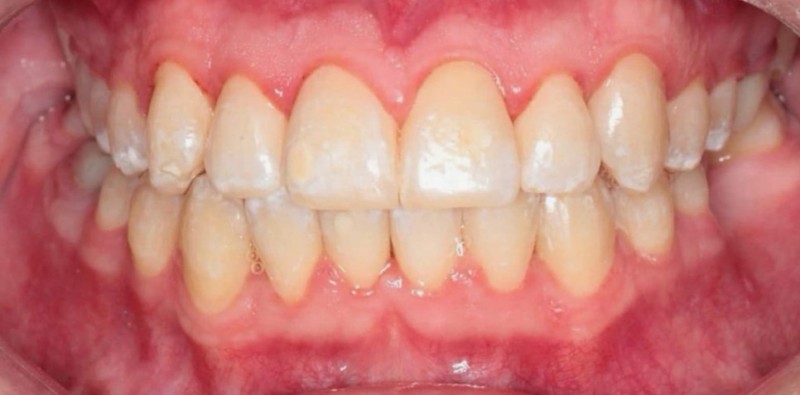

Установка металлических брекетов

Большой дефицит места на верхней челюсти в следствие чего произошло искривление зубов. Срок лечения 1 год и 5 месяцев. Металлическая брекет-система.

Доктор: Хачатрян Лариса Рубеновна